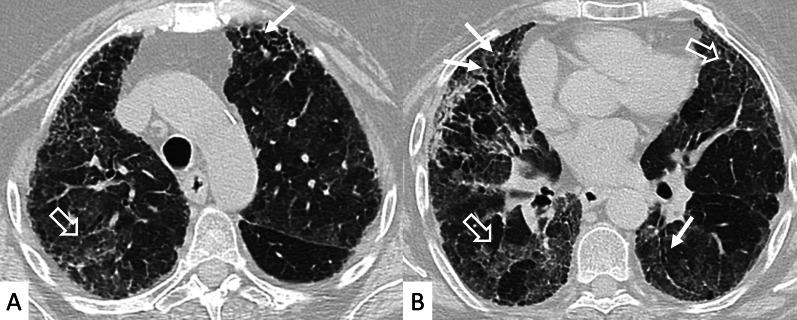

Connective tissue diseases (CTDs) include a spectrum of disorders that affect the connective tissue of the human body; they include autoimmune disorders characterized by immune-mediated chronic inflammation and the development of fibrosis. Lung involvement can be misdiagnosed, since pulmonary alterations preceded osteo-articular manifestations only in 20% of cases and they have no clear clinical findings in the early phases. All pulmonary structures may be interested: pulmonary interstitium, airways, pleura and respiratory muscles. Among these autoimmune disorders, rheumatoid arthritis (RA) is characterized by usual interstitial pneumonia (UIP), pulmonary nodules and airway disease with air-trapping, whereas non-specific interstitial pneumonia (NSIP), pulmonary hypertension and esophageal dilatation are frequently revealed in systemic sclerosis (SSc). NSIP and organizing pneumonia (OP) may be found in patients having polymyositis (PM) and dermatomyositis (DM); in some cases, perilobular consolidations and reverse halo-sign areas may be observed. Systemic lupus erythematosus (SLE) is characterized by serositis, acute lupus pneumonitis and alveolar hemorrhage. In the Sjögren syndrome (SS), the most frequent pattern encountered on HRCT images is represented by NSIP; UIP and lymphocytic interstitial pneumonia (LIP) are reported with a lower frequency. Finally, fibrotic NSIP may be the interstitial disease observed in patients having mixed connective tissue diseases (MCTD). This pictorial review therefore aims to provide clinical features and imaging findings associated with autoimmune CTDs, in order to help radiologists, pneumologists and rheumatologists in their diagnoses and management.

结缔组织病(CTDs)包括一系列影响人体结缔组织的疾病;它们包括以免疫介导的慢性炎症和纤维化发展为特征的自身免疫性疾病。肺部受累可能会被误诊,因为肺部改变仅在20%的病例中先于骨关节炎表现出现,且在早期阶段没有明确的临床发现。所有肺部结构都可能受累:肺间质、气道、胸膜和呼吸肌。在这些自身免疫性疾病中,类风湿关节炎(RA)的特征是普通型间质性肺炎(UIP)、肺结节和伴有空气潴留的气道疾病,而系统性硬化症(SSc)常表现为非特异性间质性肺炎(NSIP)、肺动脉高压和食管扩张。NSIP和机化性肺炎(OP)可见于多发性肌炎(PM)和皮肌炎(DM)患者;在某些情况下,可观察到小叶周围实变和反晕征区域。系统性红斑狼疮(SLE)的特征是浆膜炎、急性狼疮性肺炎和肺泡出血。在干燥综合征(SS)中,HRCT图像上最常见的表现是NSIP;UIP和淋巴细胞间质性肺炎(LIP)的报道频率较低。最后,纤维化NSIP可能是混合性结缔组织病(MCTD)患者中观察到的间质性疾病。因此,本图像综述旨在提供与自身免疫性CTDs相关的临床特征和影像学表现,以帮助放射科医生、呼吸科医生和风湿病科医生进行诊断和管理。